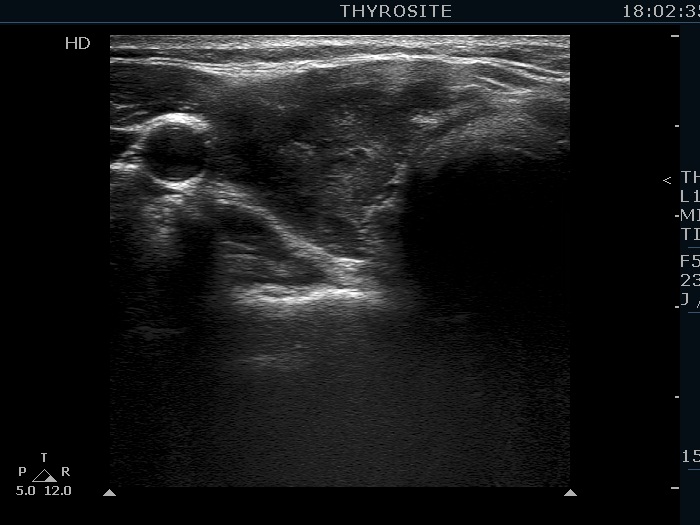

Second examination 19 months later (second row of images):

Comment. This is a typical presentation of a newly developed hypothyroidism regarding the change in echo pattern. Although the correlation between the echogenicity index and the hormonal status is week, in a particular patient, a developing hypothyroidism from an euthyroid state usually correlates with an increasing echogenicity index.Clinical data: This time the patient had no complaints, however the TSH was 16.8 mIU/L two month ago.

Laboratory tests: TSH 29.1 mIU/L, FT4 13.1 pM/L, aTPO 638 U/mL.

Ultrasonography. Compared with The previous examination, one change could be observed: the echogenicity index rose to 70-90%.